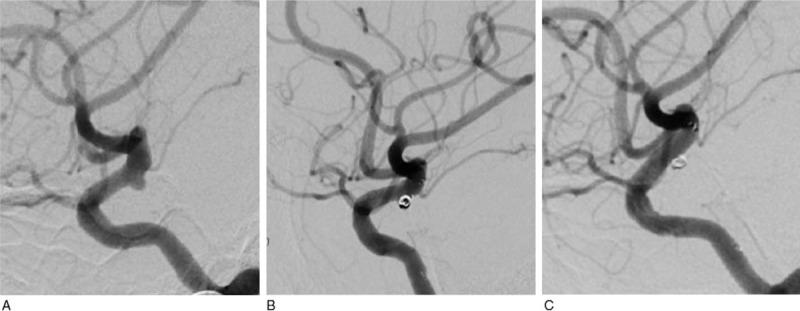

Treatments for very small (3 mm or smaller) intracranial aneurysms (VSAs) remain controversial. The aim of this study was to evaluate the efficacy of endovascular treatment for VSAs and to evaluate clinical risk factors associated with complications.This retrospective study enrolled 82 VSA patients who underwent coil embolization in our institution. Angiographic outcomes were assessed according to the Meyers classification. The clinical results were evaluated using the modified Rankin scale (mRS) immediately after coiling, at discharge, and during follow-up. A Mann-Whitney U test was performed for non-normally distributed continuous variables. A Pearson χ test or Fisher's exact test was performed for categorical variables.Among 82 aneurysms, 54 were treated with stent-assisted coiling (SAC) embolization. Thromboembolic complications were seen in 2 patients (2.4%). Intraoperative rupture occurred in 4 patients (4.9%). Other adverse events occurred in 2 patients (2.4%). Two patients (2.4%) had permanent disabling neurologic deficit (mRS 3-6) because of complications. The overall mortality rate was 1.2%. Adverse events were correlated with the location of aneurysms (P = .02), Fisher grade (P = .01), and treatment experience (P = .03). Patients with middle cerebral artery (MCA) bifurcation and anterior communicating artery (ACoA) aneurysms were more likely to experience a higher incidence of complication. Thirty-five patients underwent angiographic follow-up. The complete occlusion rate improved from an immediate 37.8% to 80.0% at follow-up.In the short term, coiling is a safe and effective approach for the treatment of VSAs. SAC may be associated with a high rate of further occlusion during short-term follow-up. Endovascular treatment of VSAs at middle cerebral artery bifurcation or anterior communicating artery is associated with a higher incidence of complications.

对于非常小(3毫米或更小)的颅内动脉瘤(VSAs),治疗方法仍存在争议。本研究的目的是评估血管内治疗VSAs的疗效,并评估与并发症相关的临床危险因素。本回顾性研究纳入了82例在我院接受弹簧圈栓塞治疗的VSA患者。根据迈耶斯分类法评估血管造影结果。在弹簧圈栓塞后即刻、出院时及随访期间,使用改良Rankin量表(mRS)评估临床结果。对非正态分布的连续变量进行曼-惠特尼U检验。对分类变量进行Pearsonχ检验或Fisher精确检验。在82个动脉瘤中,54个采用支架辅助弹簧圈栓塞(SAC)治疗。2例患者(2.4%)出现血栓栓塞并发症。4例患者(4.9%)术中发生破裂。2例患者(2.4%)出现其他不良事件。2例患者(2.4%)因并发症出现永久性致残性神经功能缺损(mRS 3 - 6)。总死亡率为1.2%。不良事件与动脉瘤位置(P = 0.02)、费希尔分级(P = 0.01)和治疗经验(P = 0.03)相关。大脑中动脉(MCA)分叉处和前交通动脉(ACoA)动脉瘤患者发生并发症的发生率更高。35例患者接受了血管造影随访。完全闭塞率从即刻的37.8%提高到随访时的80.0%。短期内,弹簧圈栓塞是治疗VSAs的一种安全有效的方法。SAC在短期随访期间可能与较高的进一步闭塞率相关。大脑中动脉分叉处或前交通动脉的VSAs血管内治疗与较高的并发症发生率相关。